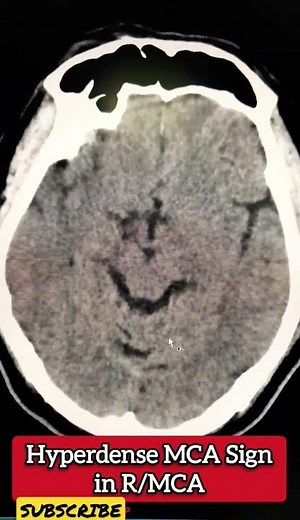

Hyperdense MCA Sign in CT - Radiology

已浏览 267 次

2023年4月16日

YouTube

Basic Radiology

Hyperdense MCA Sign

已浏览 5704 次

2019年1月1日

Dr.Hisham AlKhatib